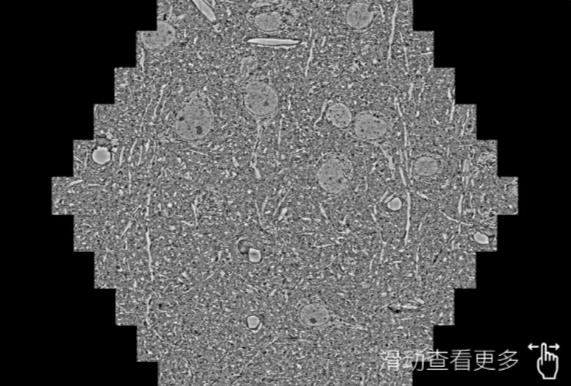

鼠脑切片。左图使用黑龙江蔡司黑龙江扫描电镜MultiSEM706对165μmx143pm面积区域成像,耗时仅需1.5秒。右图为鼠脑切片中30μm区域放大效果。样品由芝加哥大学B.Kasthuri提供。